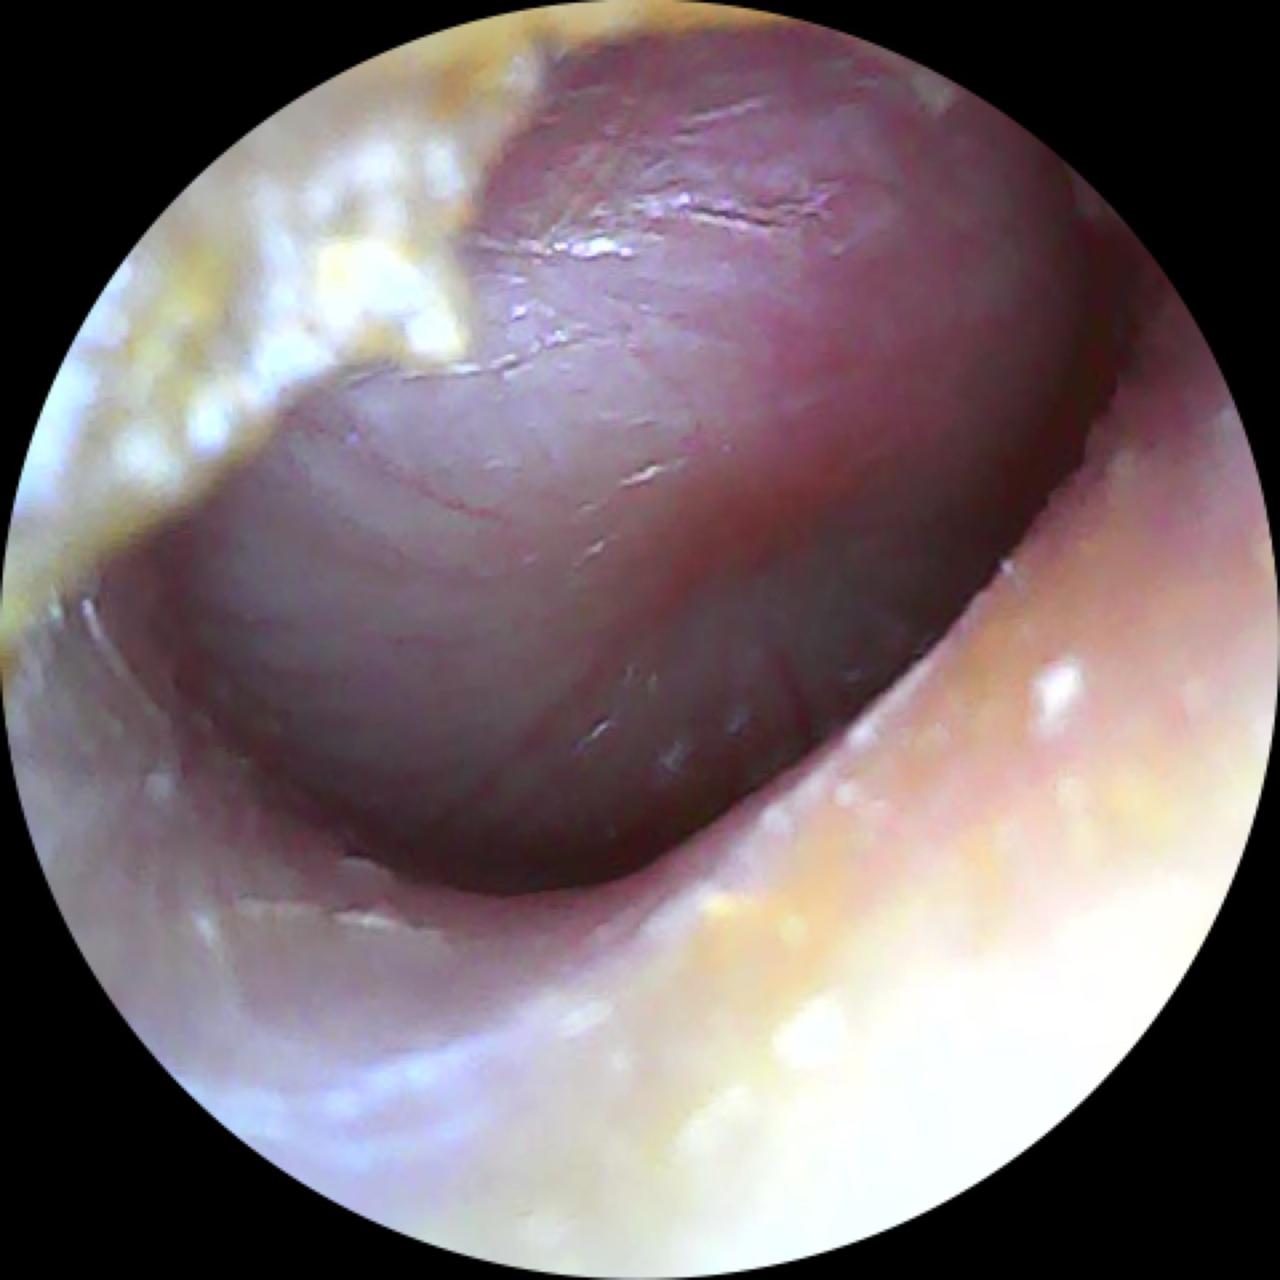

A otite média aguda é um processo inflamatório da orelha média, geralmente causado por infecções virais ou bacterianas. Ocorre quando a tuba auditiva, canal que liga a orelha média à garganta, fica bloqueada, dificultando a drenagem do muco. O resultado é o acúmulo de líquido e pus, provocando dor intensa e outros sintomas desconfortáveis. O Dr. Carlos Rezende destaca que os principais sintomas incluem dor de ouvido, febre e, possivelmente, a saída de secreção. Normalmente, a otite média aguda acompanha quadros gripais.

Os sintomas mais comuns incluem dor intensa na orelha, febre (especialmente em crianças), sensação de orelha tampada, perda auditiva temporária, e secreção em caso de perfuração do tímpano. No entanto, é importante saber diferenciar a otite média aguda de outras infecções de ouvido. O Dr. Carlos destaca que a otite média aguda é geralmente acompanhada por febre e dor, enquanto a otite média com efusão se caracteriza principalmente por redução da audição e sensação de abafamento auditivo. Além disso, a otite externa costuma causar dor, mas raramente febre, e geralmente está relacionada à manipulação do canal auditivo, como o uso frequente de hastes flexíveis.

O tratamento da otite média aguda depende da gravidade e da causa da infecção. Em muitos casos, o Dr. Carlos Rezende menciona que o tratamento pode ser feito com vigilância atenta, sem a necessidade de antibióticos. Em casos de otites recorrentes, pode ser necessária a realização de uma pequena cirurgia chamada timpanotomia com a colocação de um tubo de ventilação, para melhorar a drenagem do líquido acumulado e ventilar a orelha média.

O diagnóstico de otite média aguda é clínico, baseado na anamnese e no exame físico. O Dr. Carlos destaca que, hoje, há um grande avanço na ponderação sobre a necessidade de antibióticos, uma vez que muitos casos podem ser tratados com controle dos sintomas e monitoramento.